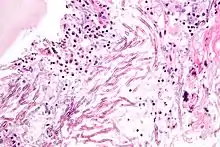

| Micrograph showing a mycosis (aspergillosis). The Aspergillus (which is spaghetti-like) is seen in the center and surrounded by inflammatory cells and necrotic debris. H&E stain. | |